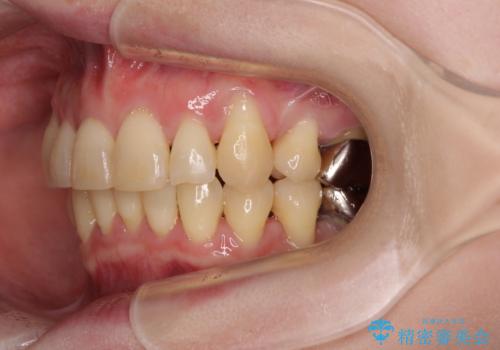

- 八重歯と正中のズレを気にして来院された患者様です。

上顎左側が八重歯になっており、上顎正中が左側にずれていました。

上顎左側の第一小臼歯を抜歯し、補助装置を用いて正中位置を改善しながら八重歯を解消していくこととしました。

下顎前歯が1本欠損していたため、上下正中の位置が合わせるという目標はなく、鼻筋に上顎正中を合わせていくように移動を行いました。